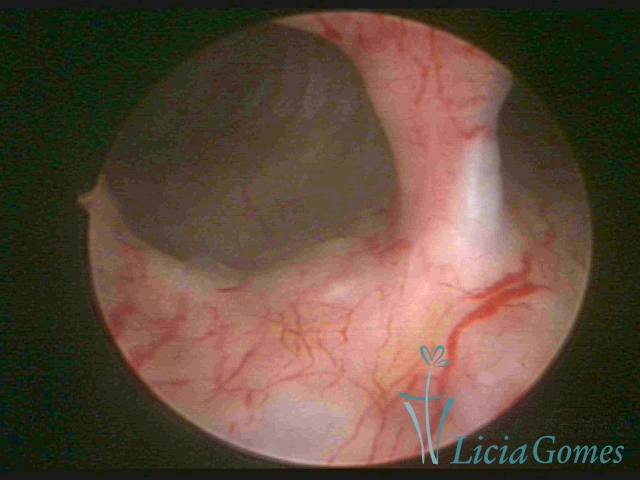

Septate uterus

It probably occurs by the lack of resorption on the middle line, in the merge of Müllerian ducts. The uterus is divided by a partial or total septum which is viewed as a crossbar, not covered by endometrium, which not bleeds when sectioned.

Complete septum when it occupies the whole extension of the cavity, dividing it into two hemicavities.

When this septum occupies only a part of the extension of the uterine cavity, it is considered as incomplete.